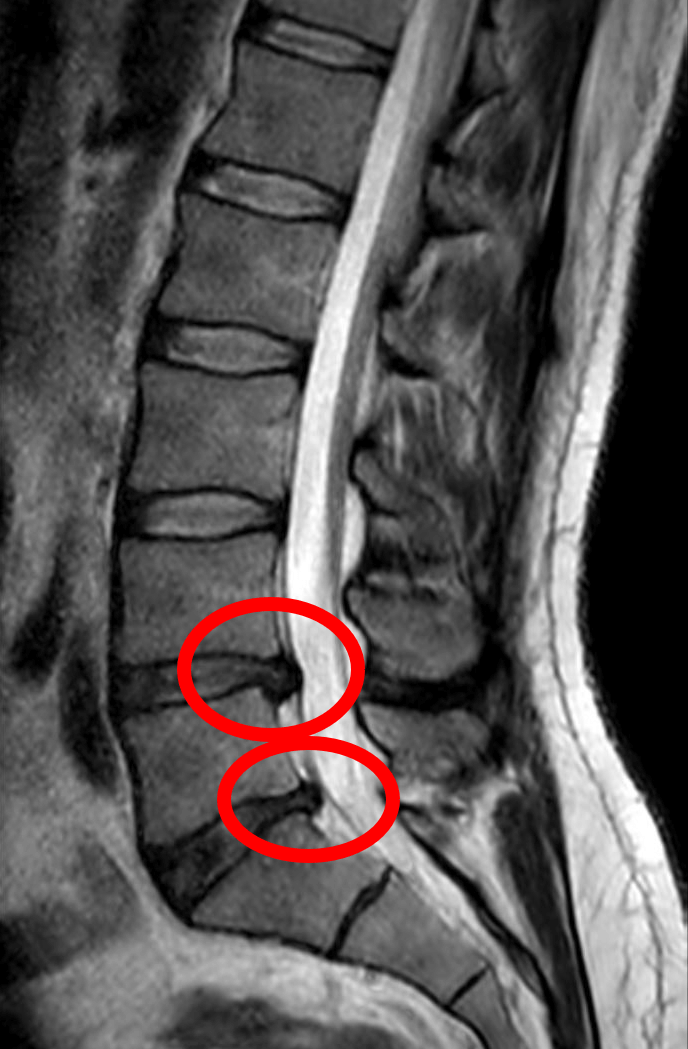

척추관 협착증은 척추 신경이 지나가는 통로인 척추관이 좁아지면서 신경이 압박을 받아 생기는 질환입니다. 노화나 과도한 육체 노동으로 인해 척추 주변의 조직이 두꺼워지거나 돌출되는 등의 변화가 발생하면서 신경 통로가 점점 좁아지는 것이 주된 원인입니다.

이러한 변화는 주로 뼈, 인대, 후관절의 퇴행성 비후로 인해 발생하며, 50~70대의 고령층에서 흔하게 나타납니다. 디스크 질환과는 달리 급성으로 발생하지 않고 서서히 진행되는 만성 질환이며, 자연적으로 회복되는 경우는 드뭅니다. 따라서 증상이 있다면 조기에 진단하고 적절한 치료를 받는 것이 중요합니다.

- 그러다가 5~10분 이상 걸으면 엉덩이나, 허벅지, 종아리가 아프고 저려서 더 걷기 어려워집니다. 이때는 앉거나 허리를 구부려야 합니다. 이를 신경성 간헐적 파행이라고 부릅니다.

- 걷다가 아플 때 앉거나 허리를 숙이면 통증이 완화되고, 서거나 걸으면 다시 악화되는 특징이 있습니다.

디스크는 물렁한 조직이므로 시간이 지나면 쪼그라들기도 하지만, 협착증은 뼈와 인대가 자라서 신경을 누르는 구조적 문제이기 때문에 자연스럽게 좋아지는 병은 아닙니다.